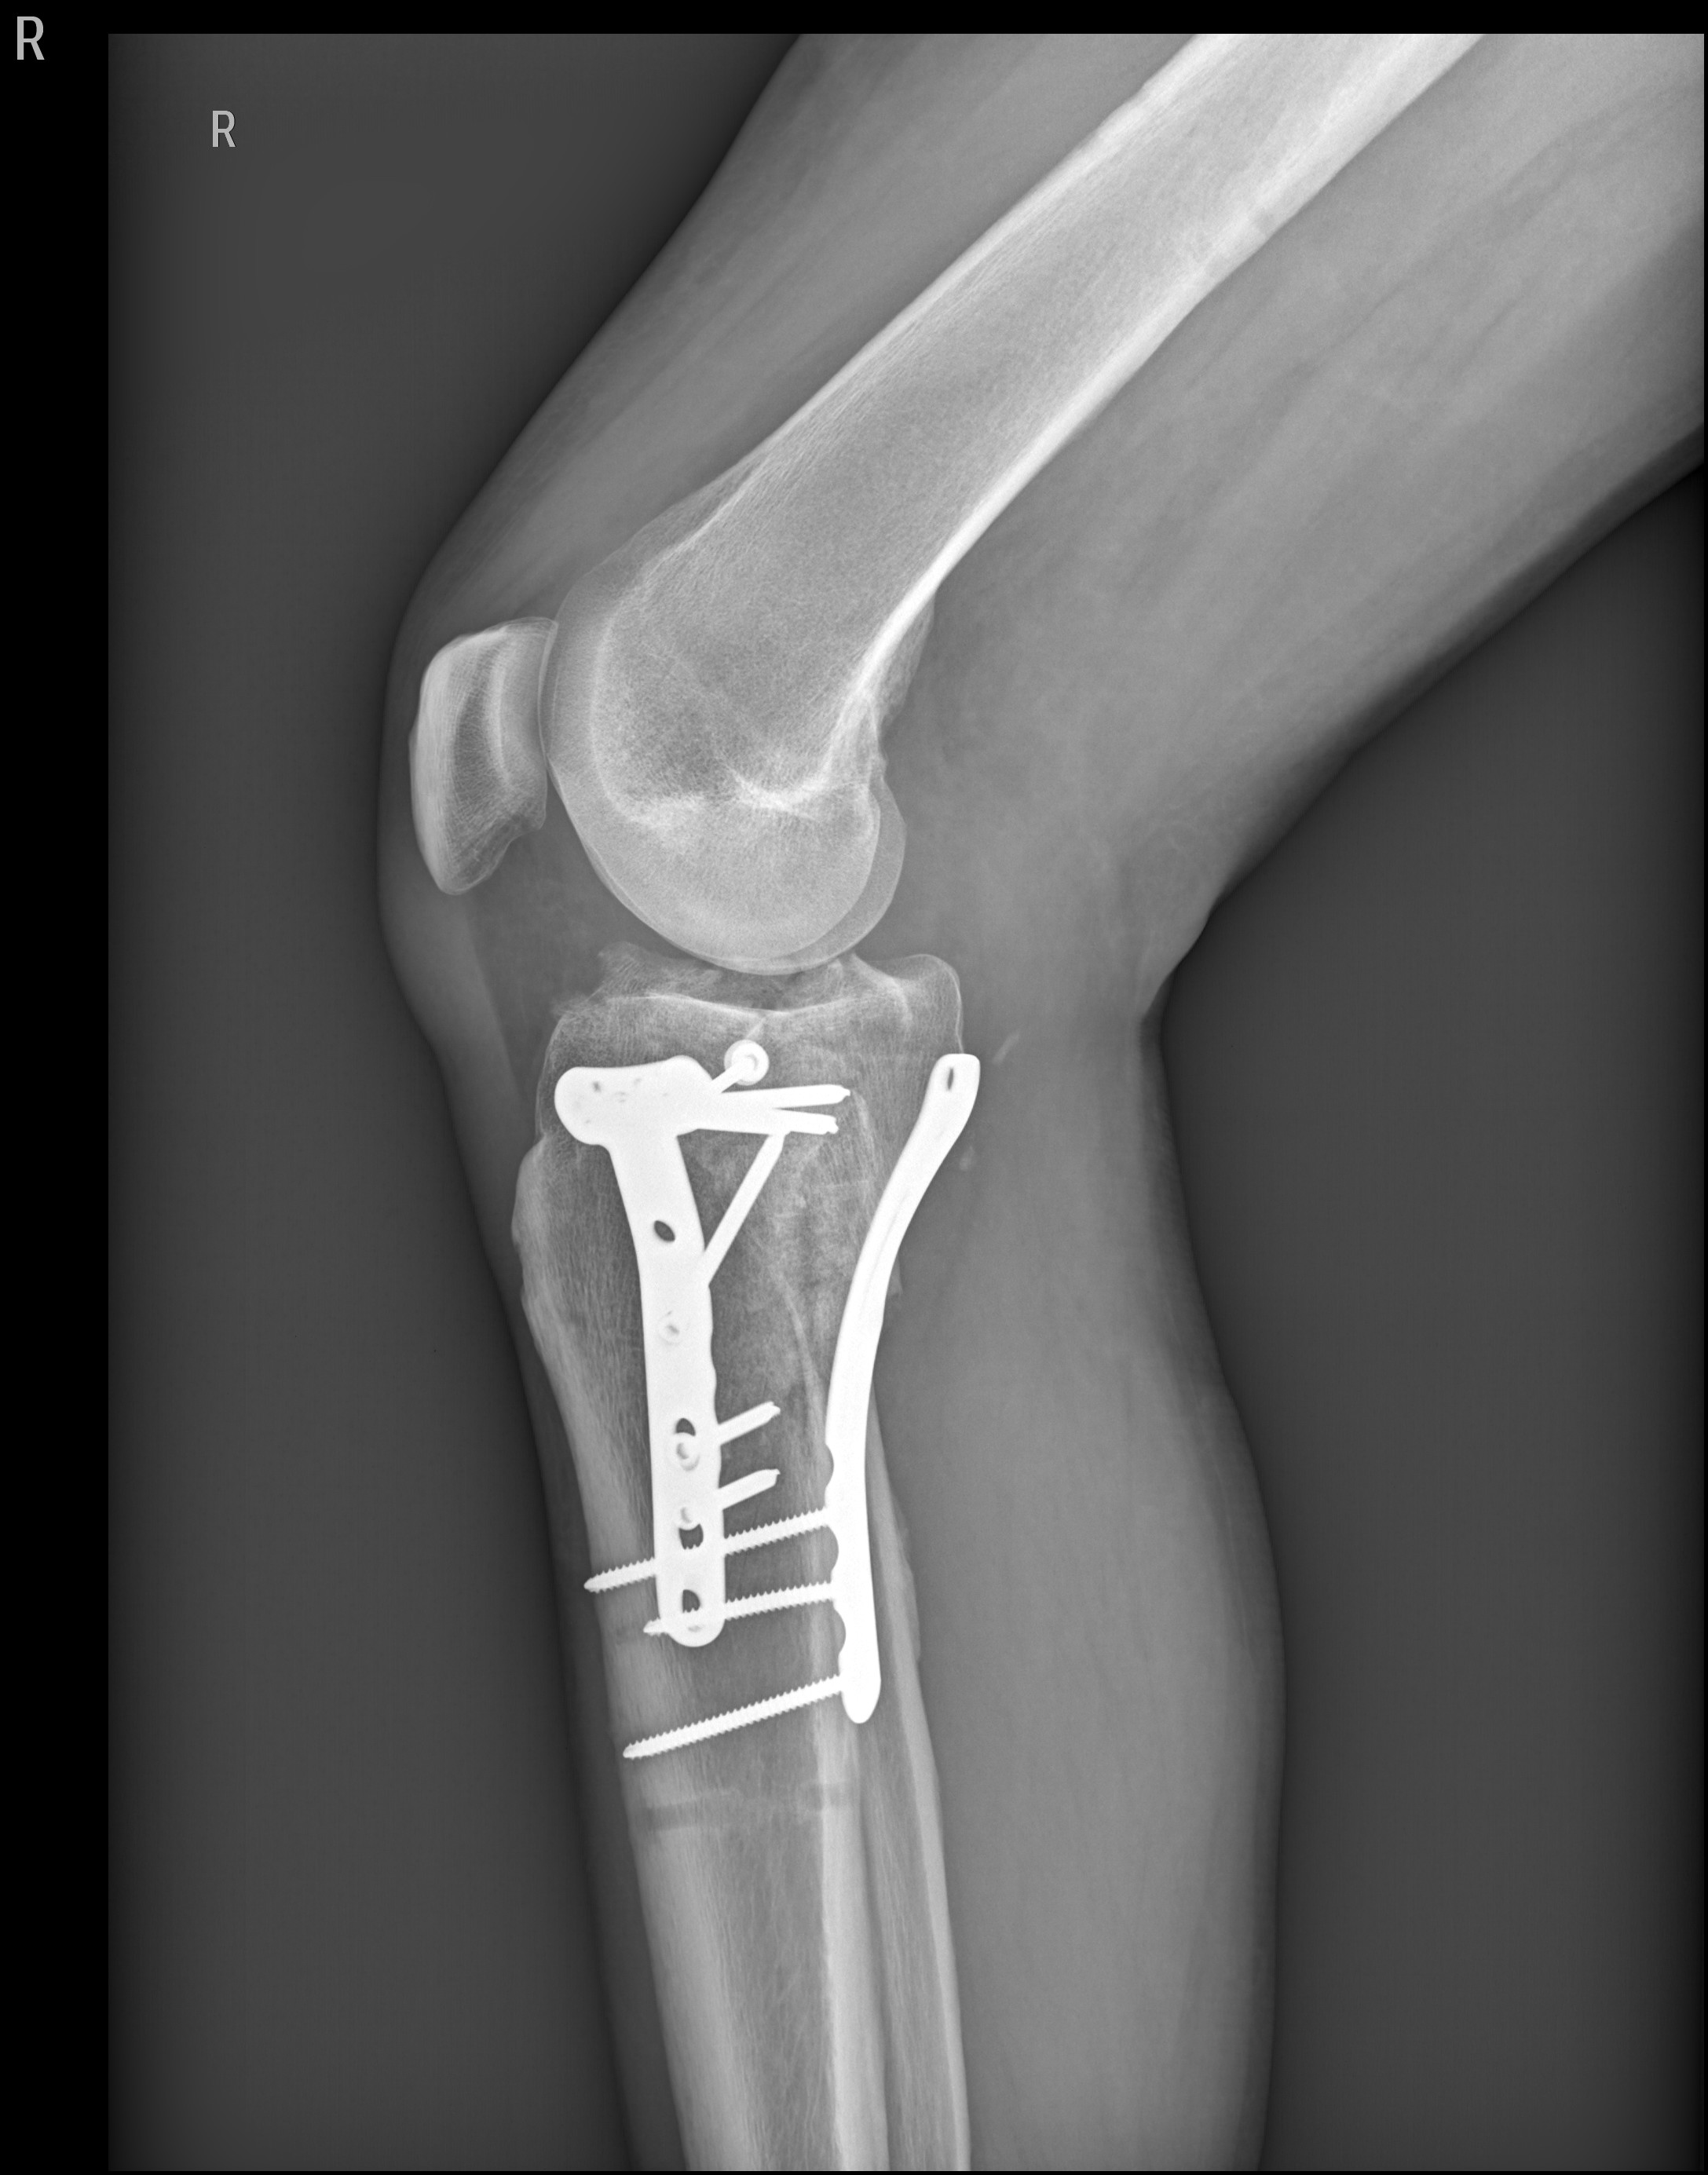

Der erste Schritt zum Cyborg ist getan.Ich hoffe, dass ich im April wieder fit bin für ......

Ein anderer User nannte sowas "enhanced" ......Der erste Schritt zum Cyborg ist getan.

Das ist genau das große Problem, Kniegelenk ist zertrümmert, auch die Kreuzbänder, Kapsel und alles drumherum, ist schwer verletzt, hoffentlich kann ich es genug dehnen um weiter zu falten, jetzt bin ich nur bei 114° unter extremer Spannung, locker bin ich bei 104°, und übe schon vom 3-7-21, 3/Woche Fisio und den Rest 3 mal/Tag Hausübungen, hoffe bis April wieder fit zu sein um zu fahren... und Gute Nacht